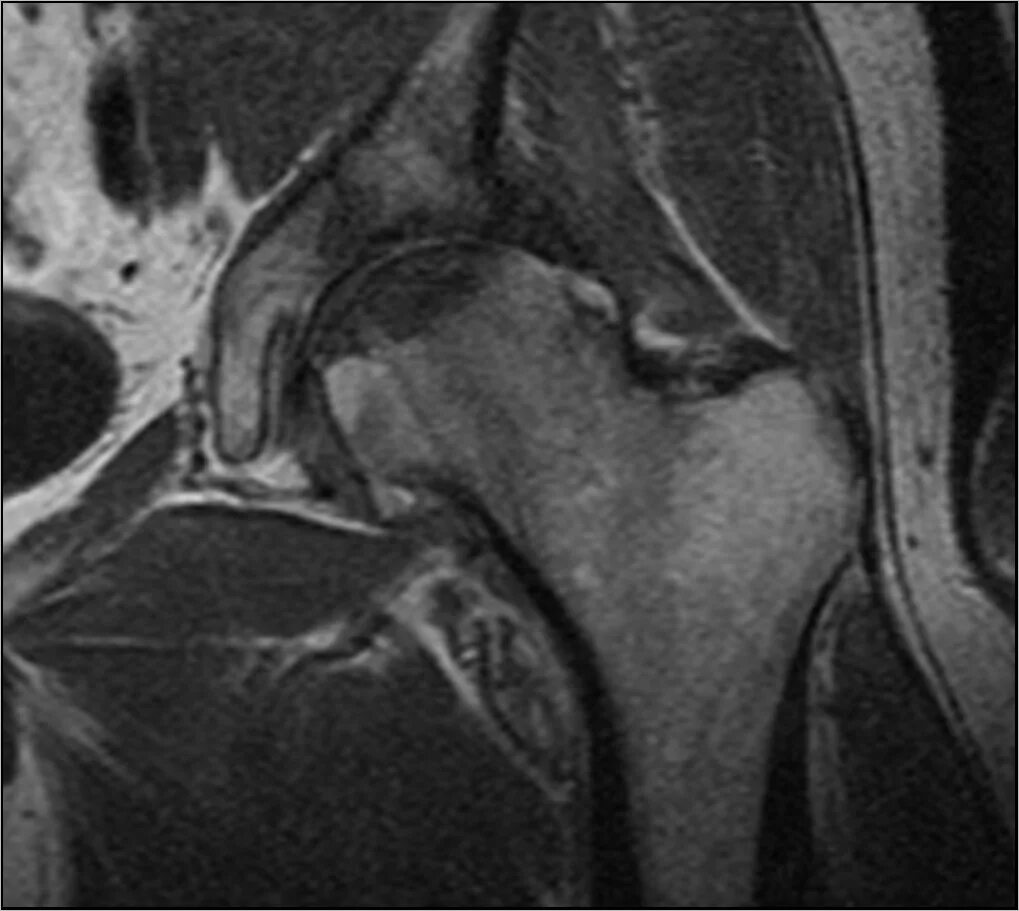

Мрт пояснично крестцового отдела тазобедренные суставы